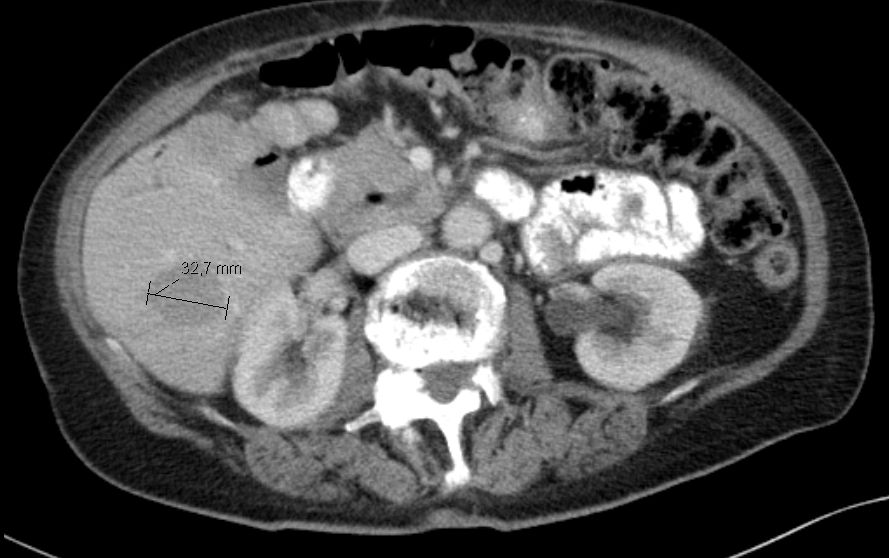

79-jährige Frau, die vor einem Jahr eine Klatskin-Tumor pT2 pNo Mo LoV1 G2 entwickelte. Operation Ro. Jetzt Lebermetastase. Chemotherapie mit Gemcitabine: Progress.![]() |